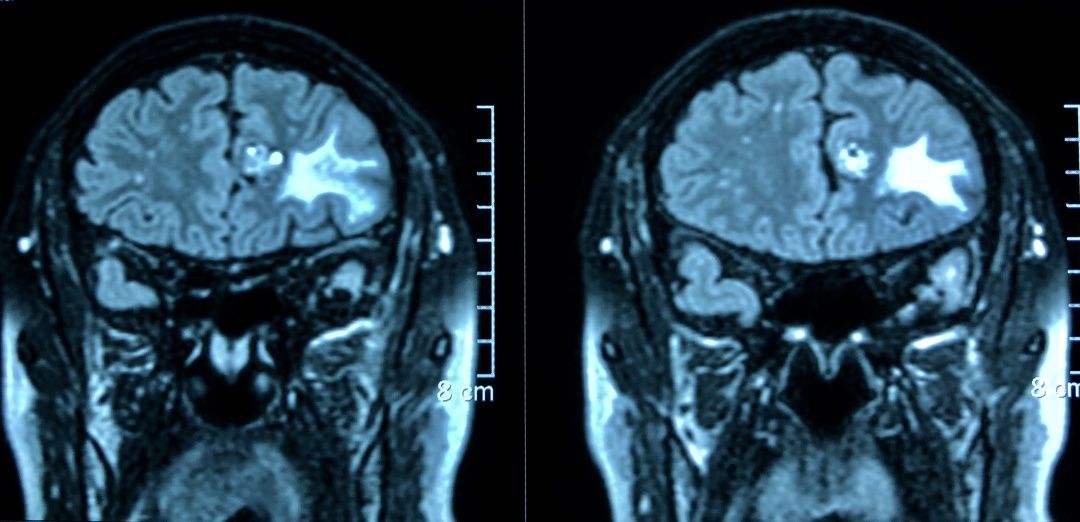

头颅MRI增强显示:左侧额叶中线旁爆米花样混杂信号肿块,双侧额叶、颞叶软化灶伴胶质增生。脑电图显示:左额有癫痫样放电。

结合CT、MRI增强、脑电图检查结果,诊断为:左侧额叶海绵状血管瘤,左额叶软化灶,患者之前的头晕、头痛症状就是因此引起。患者目前不仅有海绵状血管瘤,并且脑电波异常,虽然目前没有明显的癫痫样发作,但是以后严重了会出现临床症状,刘长青教授建议患者手术治疗,切除海绵状血管瘤,解除出血风险,同时去掉癫痫灶。